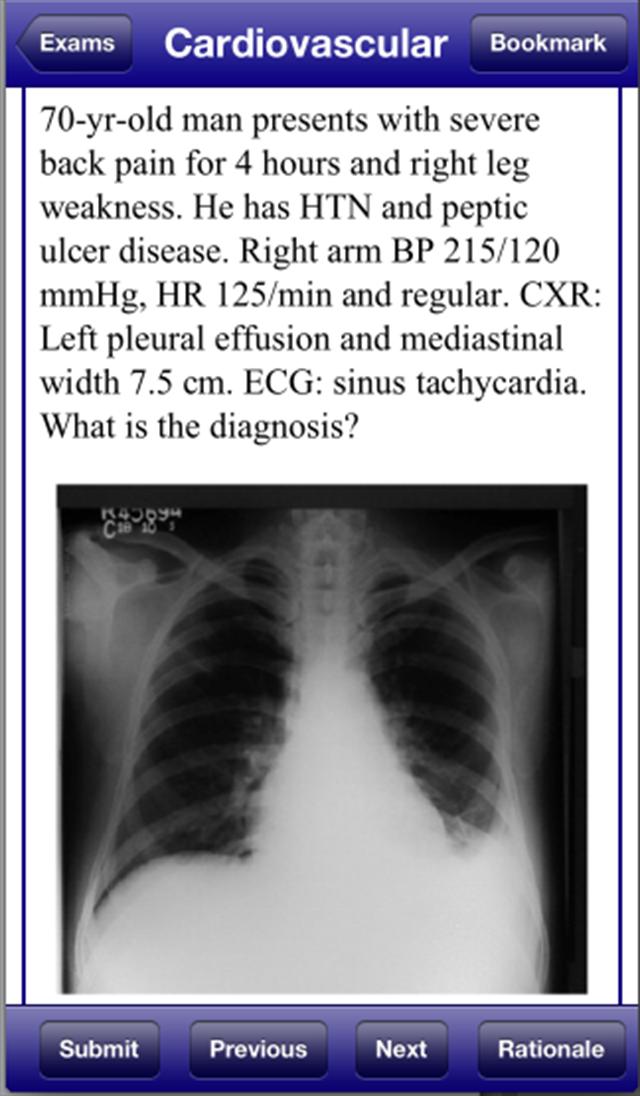

美国医学博士David Nobel的USMLE 2 Stanford Review Course ,复制了实际的USMLE步骤2临床知识检查。 USMLE 2 Stanford Review Course包括1800个问题和答案,由值得信赖的医学院教授撰写,他们审查了最新的USMLE 2考试。 USMLE 2 Stanford Review Course还包括300个图像格式问题,包括CT扫描,MRI,ECGS和皮肤病学图片。